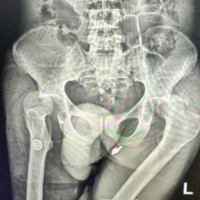

At 4-week follow-up, the patient reported improved arm pain and no longer had pain at night. She had discontinued icing and acetaminophen. Mild tenderness was noted over the mid-humerus fracture site, but she demonstrated satisfactory functional range of motion in abduction and rotation. She was neurologically intact and had full strength. Radiographs indicated reactive changes without displacement but minimal fracture healing (Fig. 2). She was advised to continue the same nonoperative plan and to minimize her strenuous activities. The patient was evaluated 14, 22, and 52 weeks after her injury to monitor for fracture healing and to ensure that no further deformation of the stem occurred. The patient demonstrated progressive improvements in pain and range of motion, returning to her usual activities, including housework and walking with her husband, without pain. At 52 weeks, radiographs confirmed complete fracture healing (Fig. 3), and she was released from our care with no further need for follow-up.